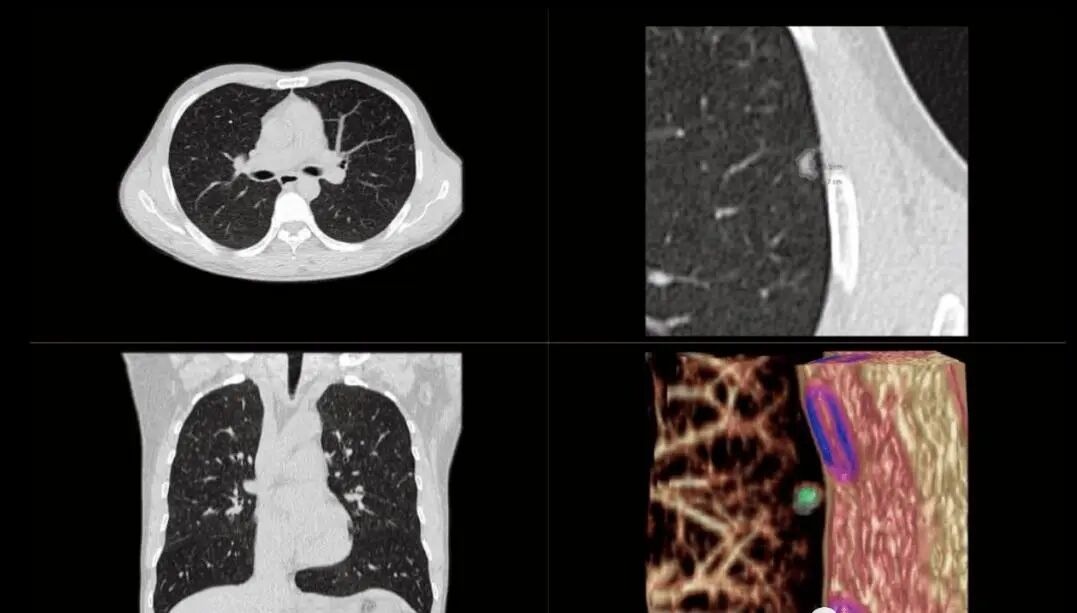

6、低剂量胸部CT检查:胸部低剂量螺旋CT扫描辐射剂量仅为常规CT的26%甚至更低,大大降低了对受检者的伤害;尤其适用于肺癌早期筛查、肺内结节的定期追踪,以及未成年人的诊疗中。